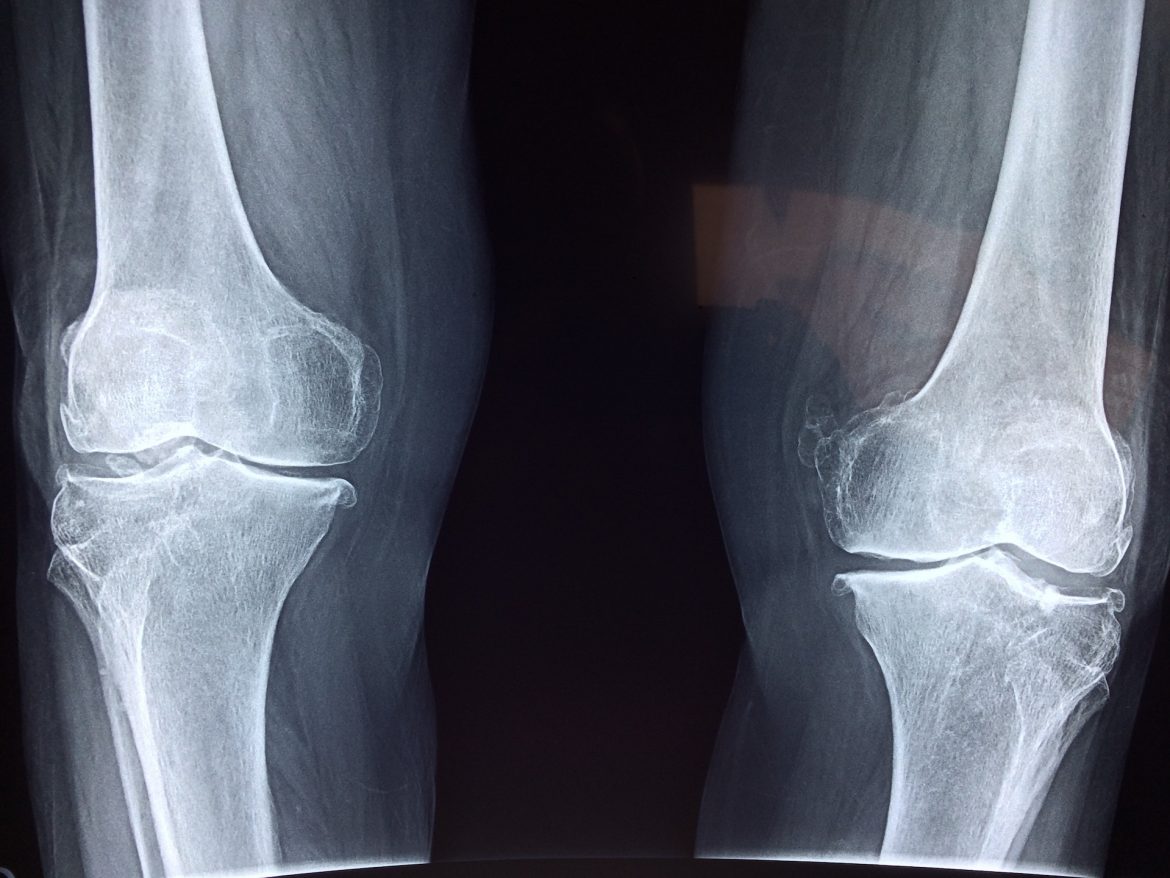

Om te kunnen begrijpen waarom de knie zo kwetsbaar is gaan we wat dieper op de anatomie in. De knie bestaat uit drie stukken bot, te weten; het femur (dijbeen) de tibia (scheenbeen) en de patella (knieschijf). Het kniegewricht is een scharnier gewricht wat inhoudt dat deze alleen kan strekken of buigen. Het femur en de tibia worden met elkaar verbonden door het kapsel en de banden. De knie kent 4 verschillende banden, twee kniebanden en twee kruisbanden. De Kniebanden bestaan uit verschillende structuurlagen. Zo bestaat de MCL (mediaal collateraal ligament) uit drie lagen. De MCL remt het naar binnen klappen van de knie en geeft stabiliteit aan het gewricht. De LCL (lateraal collateraal ligament) is de buitenste knieband en verbindt het dijbeen met het scheenbeen. Deze band beschermt het naar buitenklappen van de knie.

De twee kruisbanden zijn erg belangrijk voor de stabiliteit van het gewricht. Niet alleen verzorgen zij stabiliteit, ze geven ook informatie door over de stand en de spanning op de band. Dit zal straks een belangrijke factor zijn tijdens de revalidatie. Er zijn dus twee kruisbanden, de voorste kruisband (ACL) en de achterste kruisband (PCL). De kruisbanden zorgen ervoor dat het femur en het de tibia niet naar voren of naar achteren verschuiven ten opzichte van elkaar. Bij het afscheuren van een van de kruisbanden word de knie instabiel.